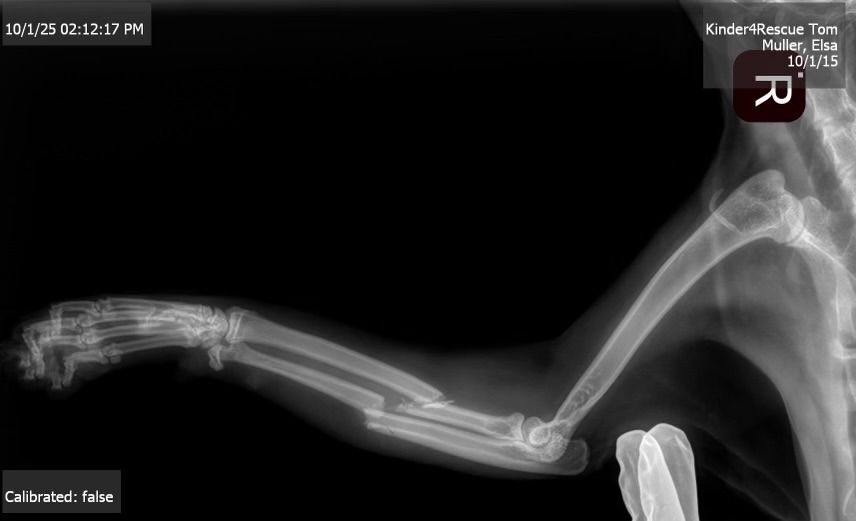

“Family and friends, my beloved Tom had an accident where a large bed frame fell on him and broke his arm. He is in a lot of pain and unfortunately needs surgery. It's going to cost an arm and a leg (no pun intended). Any amount is greatly appreciated.”